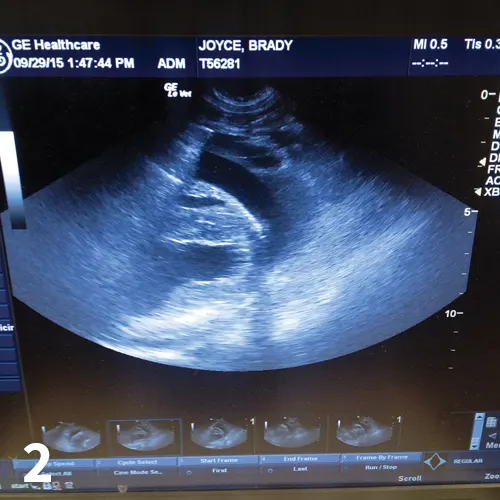

Diagnosis may be based on clinical signs, thoracic radiographs documenting a globoid cardiac silhouette (Figure 1), or ultrasonography (Figure 2). If possible, a complete cardiac ultrasound examination should be performed before pericardiocentesis, as the effusion will help delineate a mass.

Pericardial effusion on ultrasonography